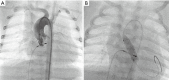

Figure 2

Patient with HLHC and stenotic PDA. (A) Lateral 90°: PDA, almost closed, is crossed with a soft coronary wire from the aortic side; (B) lateral 90°: balloon dilatation of the stenotic PDA with an angioplasty balloon (3.5 mm × 15 mm Trek, Abbott); (C) lateral 90°: delineation of the PDA after balloon angioplasty reveals still a stenotic PDA. (D) Lateral 90°: after crossing of the PDA from the venous side, a balloon-expandable stent (Formula 6 mm × 16 mm, Cook) is brought into position. A wire and a catheter in the aorta serve as marker of the aortic duct junction and therefore enable exact positioning of the stent before inflation; (E) RAO 30°: is in most cases the best angle for visualizing the aortic duct junction. Wire in the aortic arch shows that the stent covers just the PDA and is not protruding into the aorta; (F) lateral 90°: implanted stent with now patent PDA. HLHC, hypoplastic left heart complex; PDA, persistent ductus arteriosus; RAO, right anterior oblique.